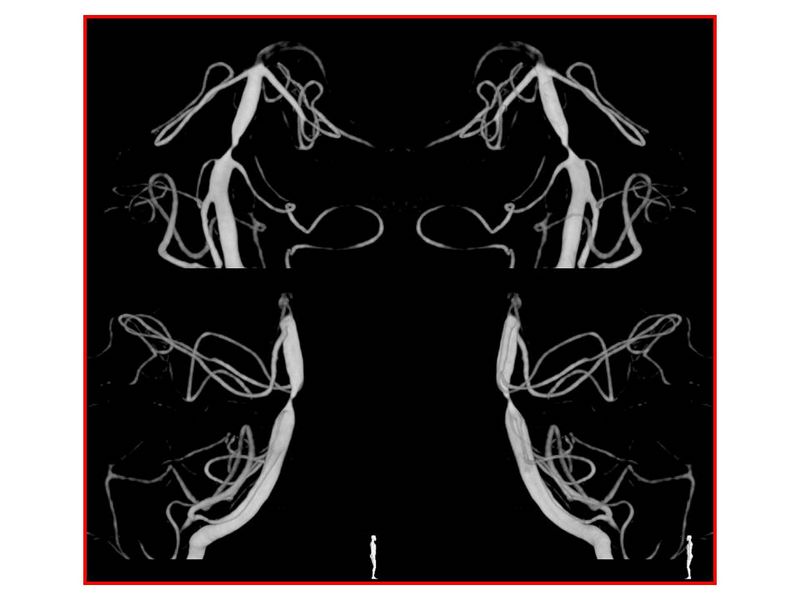

Estenosis Basilar